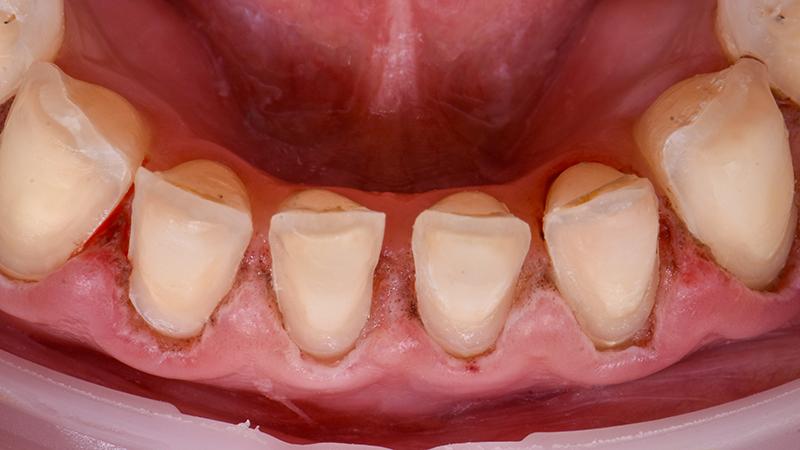

Fig. 01 : photographie et radiographie de la situation initiale.

Fig. 04 : préparations contemporaines.